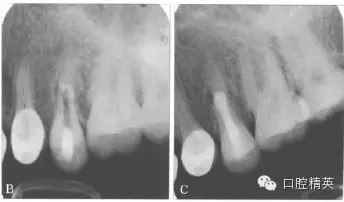

根管內(nèi)封vitapex糊劑1個(gè)月。第2次復(fù)診時(shí)瘺管已經(jīng)消退,顯微鏡下見根管內(nèi)斷端創(chuàng)面為肉芽組織,斷端直徑約為3 mm×3 mm,采用MTA連接斷端(圖4左),置生理鹽水小棉捻,氧化鋅暫封。3 d后MTA已硬化,注射熱牙膠封閉根管上段,樹脂修復(fù),降低咬合(圖4右)。

圖4 X線片。左:MTA連接斷端;右:充填片;